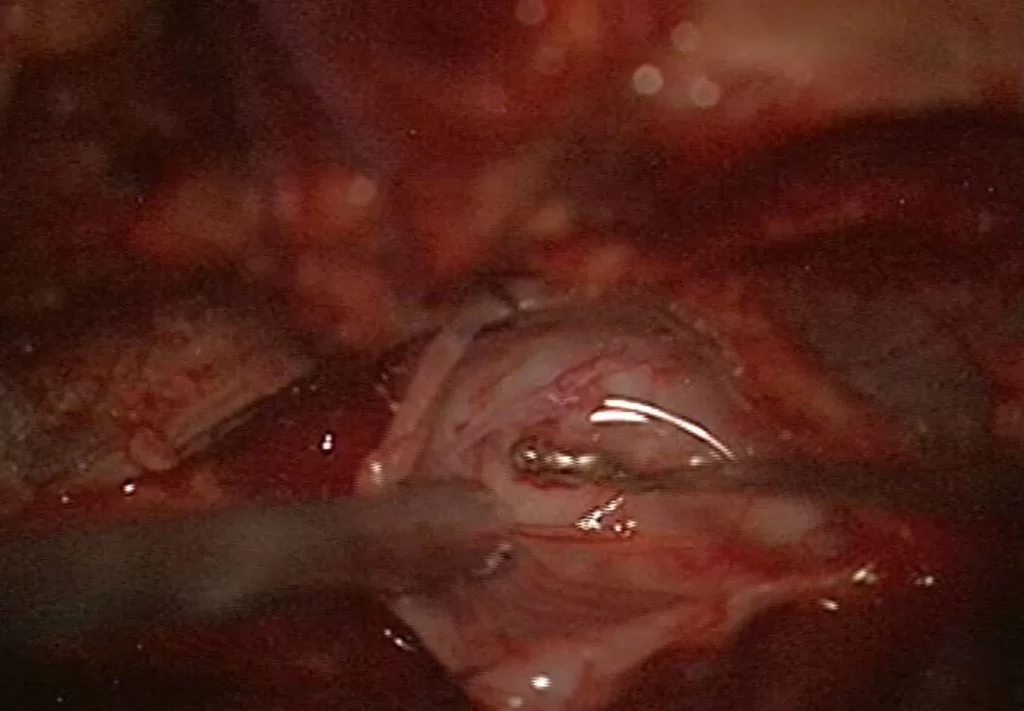

Προσωπικό αρχείο νευροχειρουργού Π. Σταυρινού

Αν τα συμπτώματα του ασθενούς ταιριάζουν με αυτά που προκαλούν οι κύστεις (κυρίως πόνος στην περιγεννητική περιοχή, πόνος στο κάθισμα και κυστικές διαταραχές) τότε αρχικά κάνω μια παρακέντηση της κύστης υπό αξονικό τομογράφο. Μ’ αυτόν τον τρόπο μειώνεται άμεσα η πίεση εντός της κύστης. Αν τα συμπτώματα του ασθενούς βελτιωθούν παροδικά, τότε προχωρώ σε χειρουργική επέμβαση. Αυτή συνήθως περιλαμβάνει διάνοιξη και θυριδοποίηση της κύστης και σύγκλιση του βαλβιδικού μηχανισμού.